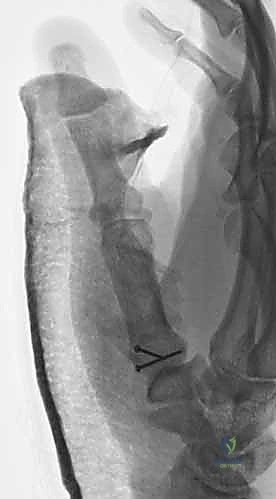

1. الرد المغلق والتثبيت عبر الجلد بالإبر (CRPP - Closed Reduction and Percutaneous Pinning)

هذا الإجراء هو الخيار المفضل لكسور "بينيت" التي يمكن إعادتها لمكانها بدون فتح جراحي كبير.

* الخطوات: يتم إجراء العملية تحت التخدير الموضعي أو الكلي. باستخدام جهاز الأشعة السينية المباشر في غرفة العمليات (C-arm Fluoroscopy)، يقوم البروفيسور هطيف برد الكسر إلى مكانه المثالي.

* بعد ذلك، يتم إدخال إبر معدنية دقيقة (K-wires أو Kirschner wires) عبر الجلد مباشرة لتثبيت قاعدة المشط الأول بالعظم المربعي، وأحياناً بالمشط الثاني لزيادة الاستقرار.

* الميزة: شقوق صغيرة جداً، ألم أقل، وشفاء أسرع. يتم إزالة هذه الإبر عادة في العيادة بعد 4 إلى 6 أسابيع.